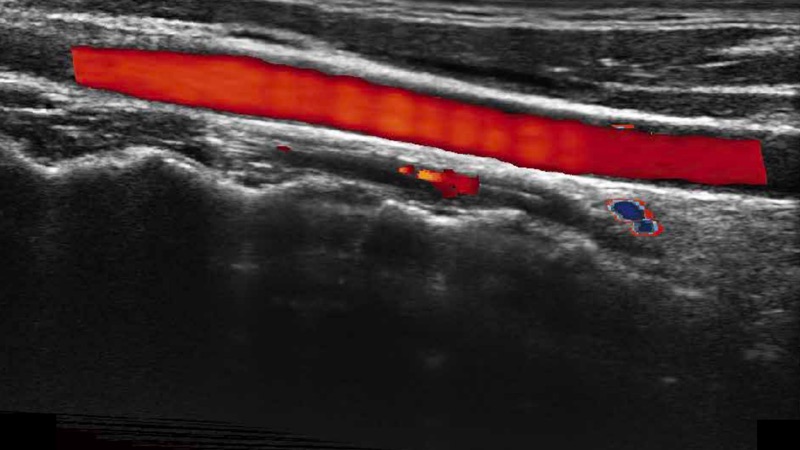

高分辨率血流成像技术提高了对低速血流信号的检测能力。在提高空间分辨率的同时,也克服了血流外溢现象,为用户提供更加真实的血流动力学信息。

凸阵、线阵和相控阵探头进行实时扫描时,开启扩展成像模式,可以扩展超声图像视野,以便更完整地查看大的病灶或组织器官的解剖结构。

通过色彩血流和实时宽景相结合,可观察到完整的静脉或动脉的血流,方便医生检查。实时扫查过程中,如有任何操作失误也可以很容易地进行回扫擦除,而不会中断扫查。